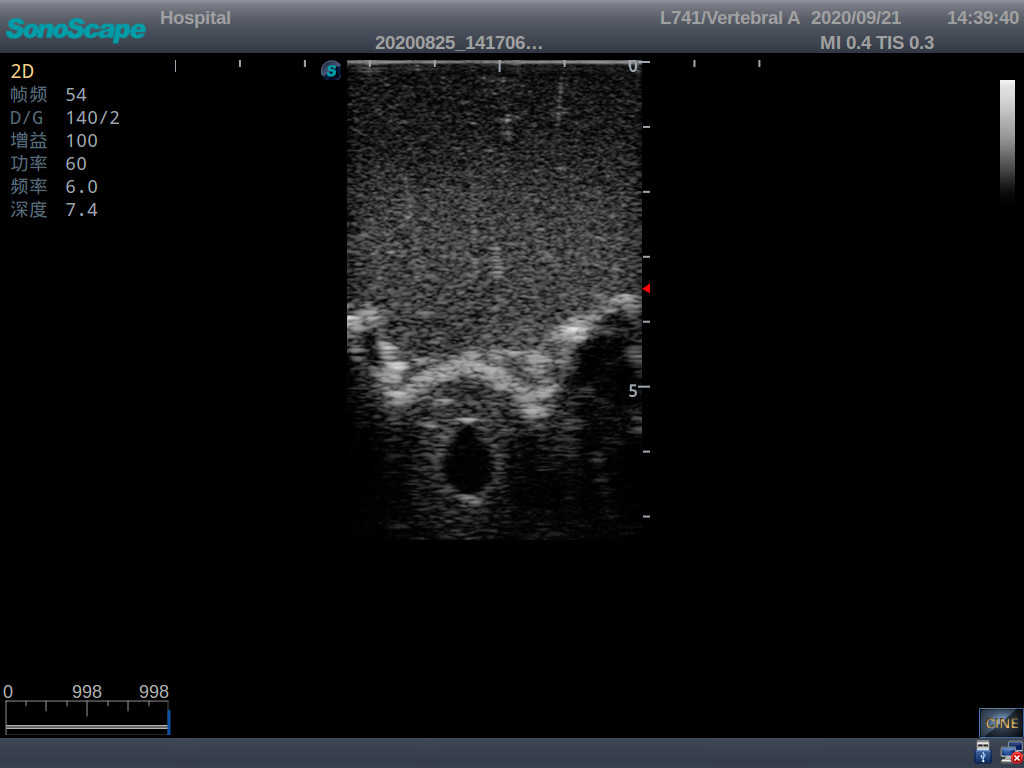

This model is an ideal choice for ultrasound-guided adult lumbar puncture training with true-to-life skin feel and touch, accurate anatomical structures as well as real clinical ultrasound images. Realistic resistance to needle tips and correct landmarks provide excellent hands-on experience.

2)  Real clinical ultrasound images